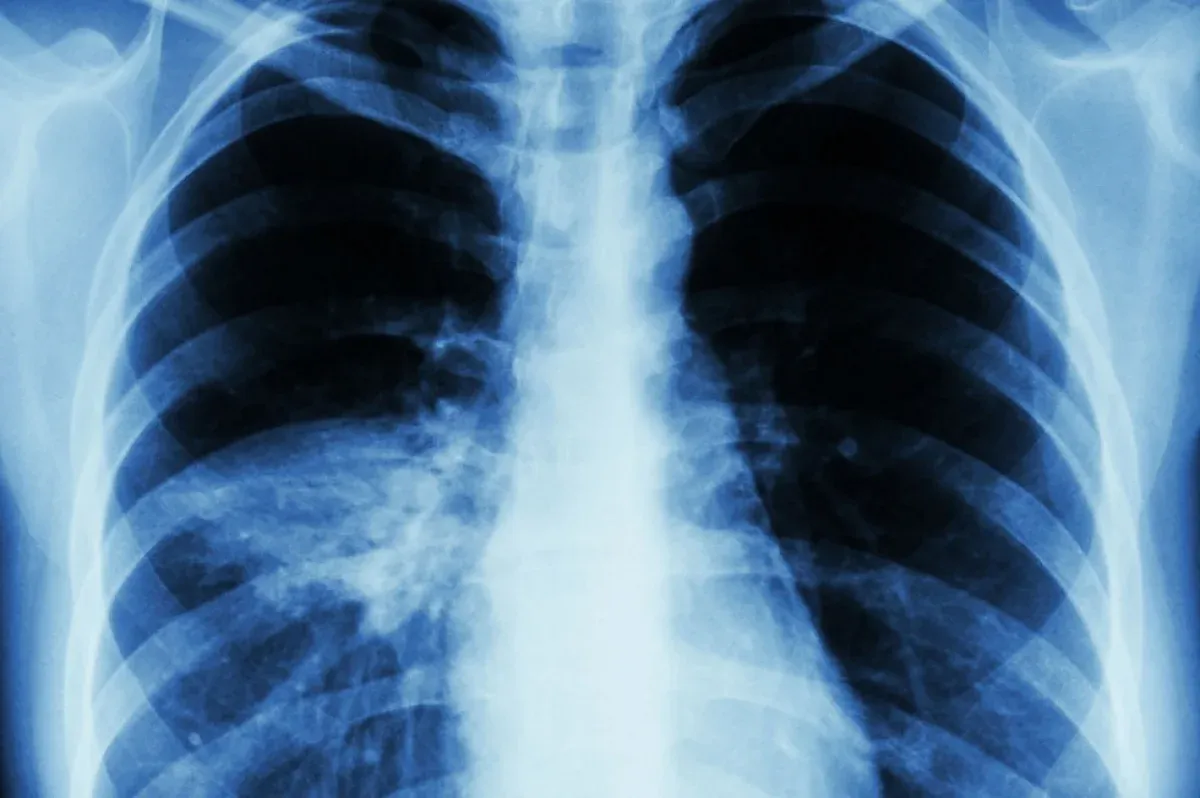

В Татарстане медики назвали опасные признаки пневмонии

Специалисты территориального управления Роспотребнадзора по Татарстану назвали ключевые признаки воспаления лёгких, при появлении которых необходимо без промедления обращаться к врачу.